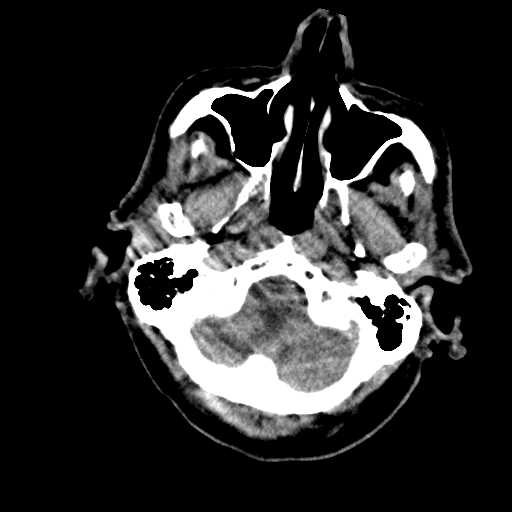

Figure 1: Illustrative examples of different types of brain hemorrhages in CT scans. The hemorrhagic regions are highlighted in red. (a) IPH, (b) IVH, (c) EDH, (d) SAH, (e) SDH.

The dataset used in this study was collected from two medical centers in Tehran, Iran: Rasoul Akram Hospital and Firouzabadi Hospital, over a period spanning 2018 to 2024. All CT scans were manually labeled hierarchically by two board-certified neurosurgeons to ensure accurate classification of ICH subtypes. The labeling process involved an initial annotation by one neurosurgeon, followed by validation and verification by a second expert to minimize errors and inconsistencies. Fig. 1 illustrates representative examples of different ICH subtypes in brain CT scans. The hemorrhagic regions are highlighted in red for better visualization. These annotated examples provide insight into the distinct imaging characteristics of each hemorrhage type, emphasizing the variability in their locations and appearances within the brain. The study received ethical approval, and data collection was conducted in compliance with institutional review board (IRB) regulations and the Declaration of Helsinki, ensuring patient confidentiality and adherence to ethical standards.